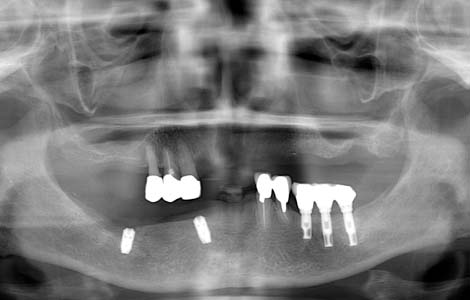

すれ違いはインプラント

入れ歯を外した時に、上下の歯が1箇所も噛み合わない状態を、「すれ違い咬合」と呼びます。この様な状態の方に入れ歯を作っても、噛むたびに歯がない方が大きく沈み込んしまうため、入れ歯ががたつき満足してもらえることはありません。この症例では、下の入れ歯を何度作っても痛くて噛めないという訴えでした。右下に傷がありました。

インプラントで入れ歯の沈みこみを抑える

解決策は、歯を抜いて総入れ歯にすることで入れ歯の沈みこみを均等にするか、インプラントを入れて入れ歯の沈みこみを抑えるようにするしかありません。この症例では右下に2本のインプラントを入れました。これで右下の入れ歯の沈みこみが防げるようになったので、痛みもなくお食事ができるようになりました。